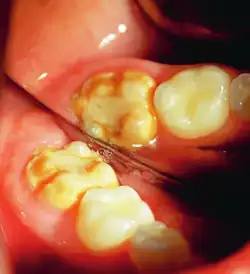

Enamel hypocalcification is characterized by the presence of white spots or streaks on the teeth due to reduced mineral content,[34] posing both cosmetic concerns and potential structural weaknesses. White spots can also be seen in patients. As the enamel undergoes demineralization, it becomes thinner, often leading to yellow or brown discoloration. The severity of this discoloration can range from mild yellowing to more pronounced brown staining, reflecting the extent of enamel loss.[7] This compromised enamel layer can also heighten tooth sensitivity to temperature changes and sugary foods, as external stimuli more easily reach the pulp, causing discomfort. Additionally, individuals with enamel hypocalcification experience a higher incidence of dental caries, as the weakened enamel provides less resistance to acid produced by oral bacteria.[19]

Clinical manifestations

Enamel hypocalcification is characterized by visible defects in the enamel, often manifesting as white spot lesions or brown discolorations.[35] In cases such as dental fluorosis, this may include mottled patterns on the enamel surface which vary in appearance and extent based on the severity of the condition.[36] In advanced cases, the mottled appearance of the enamel can expose the underlying dentin, creating an uneven and sometimes porous surface. Though the matrix of the enamel initially forms to a typical thickness, the mineralization or calcification process is incomplete or deficient, leading to softer and structurally compromised enamel.[35]

This compromised enamel is more susceptible to staining due to its rougher surface texture and increased permeability, which allows pigments and external elements to penetrate more easily. The weakened enamel may begin to wear away, especially on the occlusal surfaces of the molars, where mechanical forces are most intense. In some individuals affected by severe enamel hypocalcification, the structural deficiencies also contribute to anterior open bite where the upper and lower front teeth do not meet when biting down. This malocclusion can further complicate both functional and aesthetic aspects of the dentition.[37]